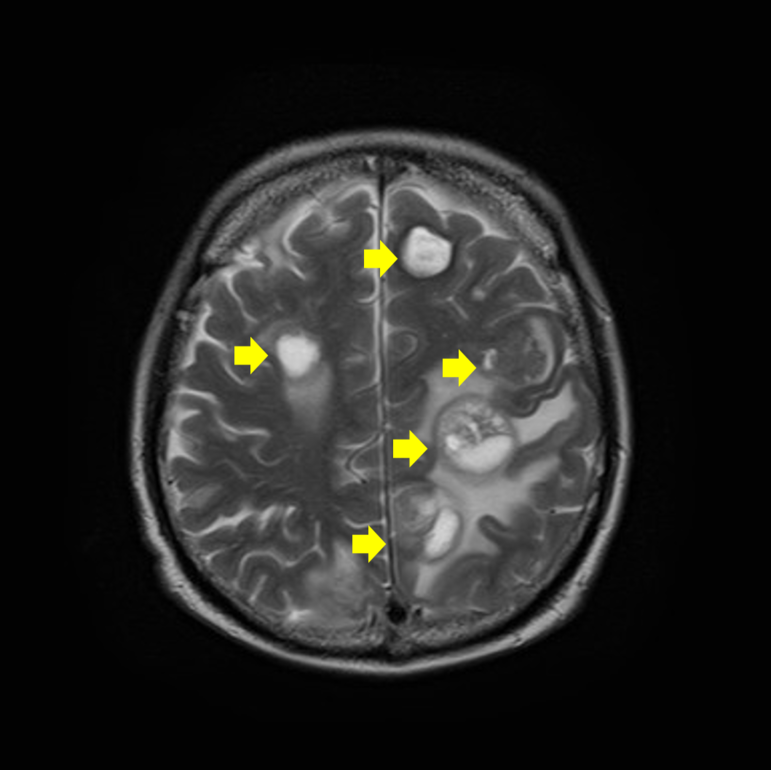

Magnetic Resonance Image:磁気共鳴画像の略。磁場の中で起こる体内の水素分子の振動をコンピューターで解析し、詳細な画像を作ります。CTだけでは分かりにくい頭部や骨への転移を調べるためには有効な検査です。より正確な診断を行うため、ガドリニウム造影剤を静脈から注射する造影MRIが用いられます。